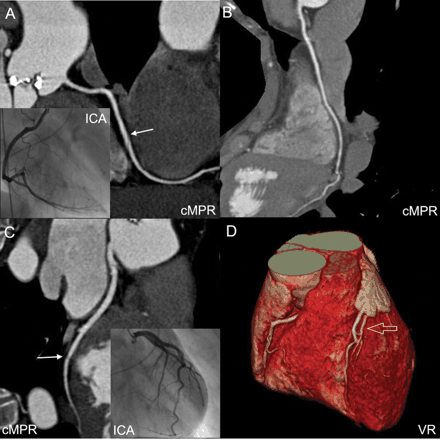

CT Coronary Angiogram (CTCA)

CTCA is a heart imaging test that helps determine if plaque buildup has narrowed a patient's coronary arteries, the blood vessels that supply the heart. Plaque is made of various substances circulating in the blood, such as fat, cholesterol and calcium that deposit along the inner lining of the arteries. Plaque, which builds up over time, can reduce or in some cases completely block blood flow.Patients undergoing a CCTA scan receive an iodine-containing contrast material (dye) as an intravenous (IV) injection to ensure the best possible images of the heart blood vessels.